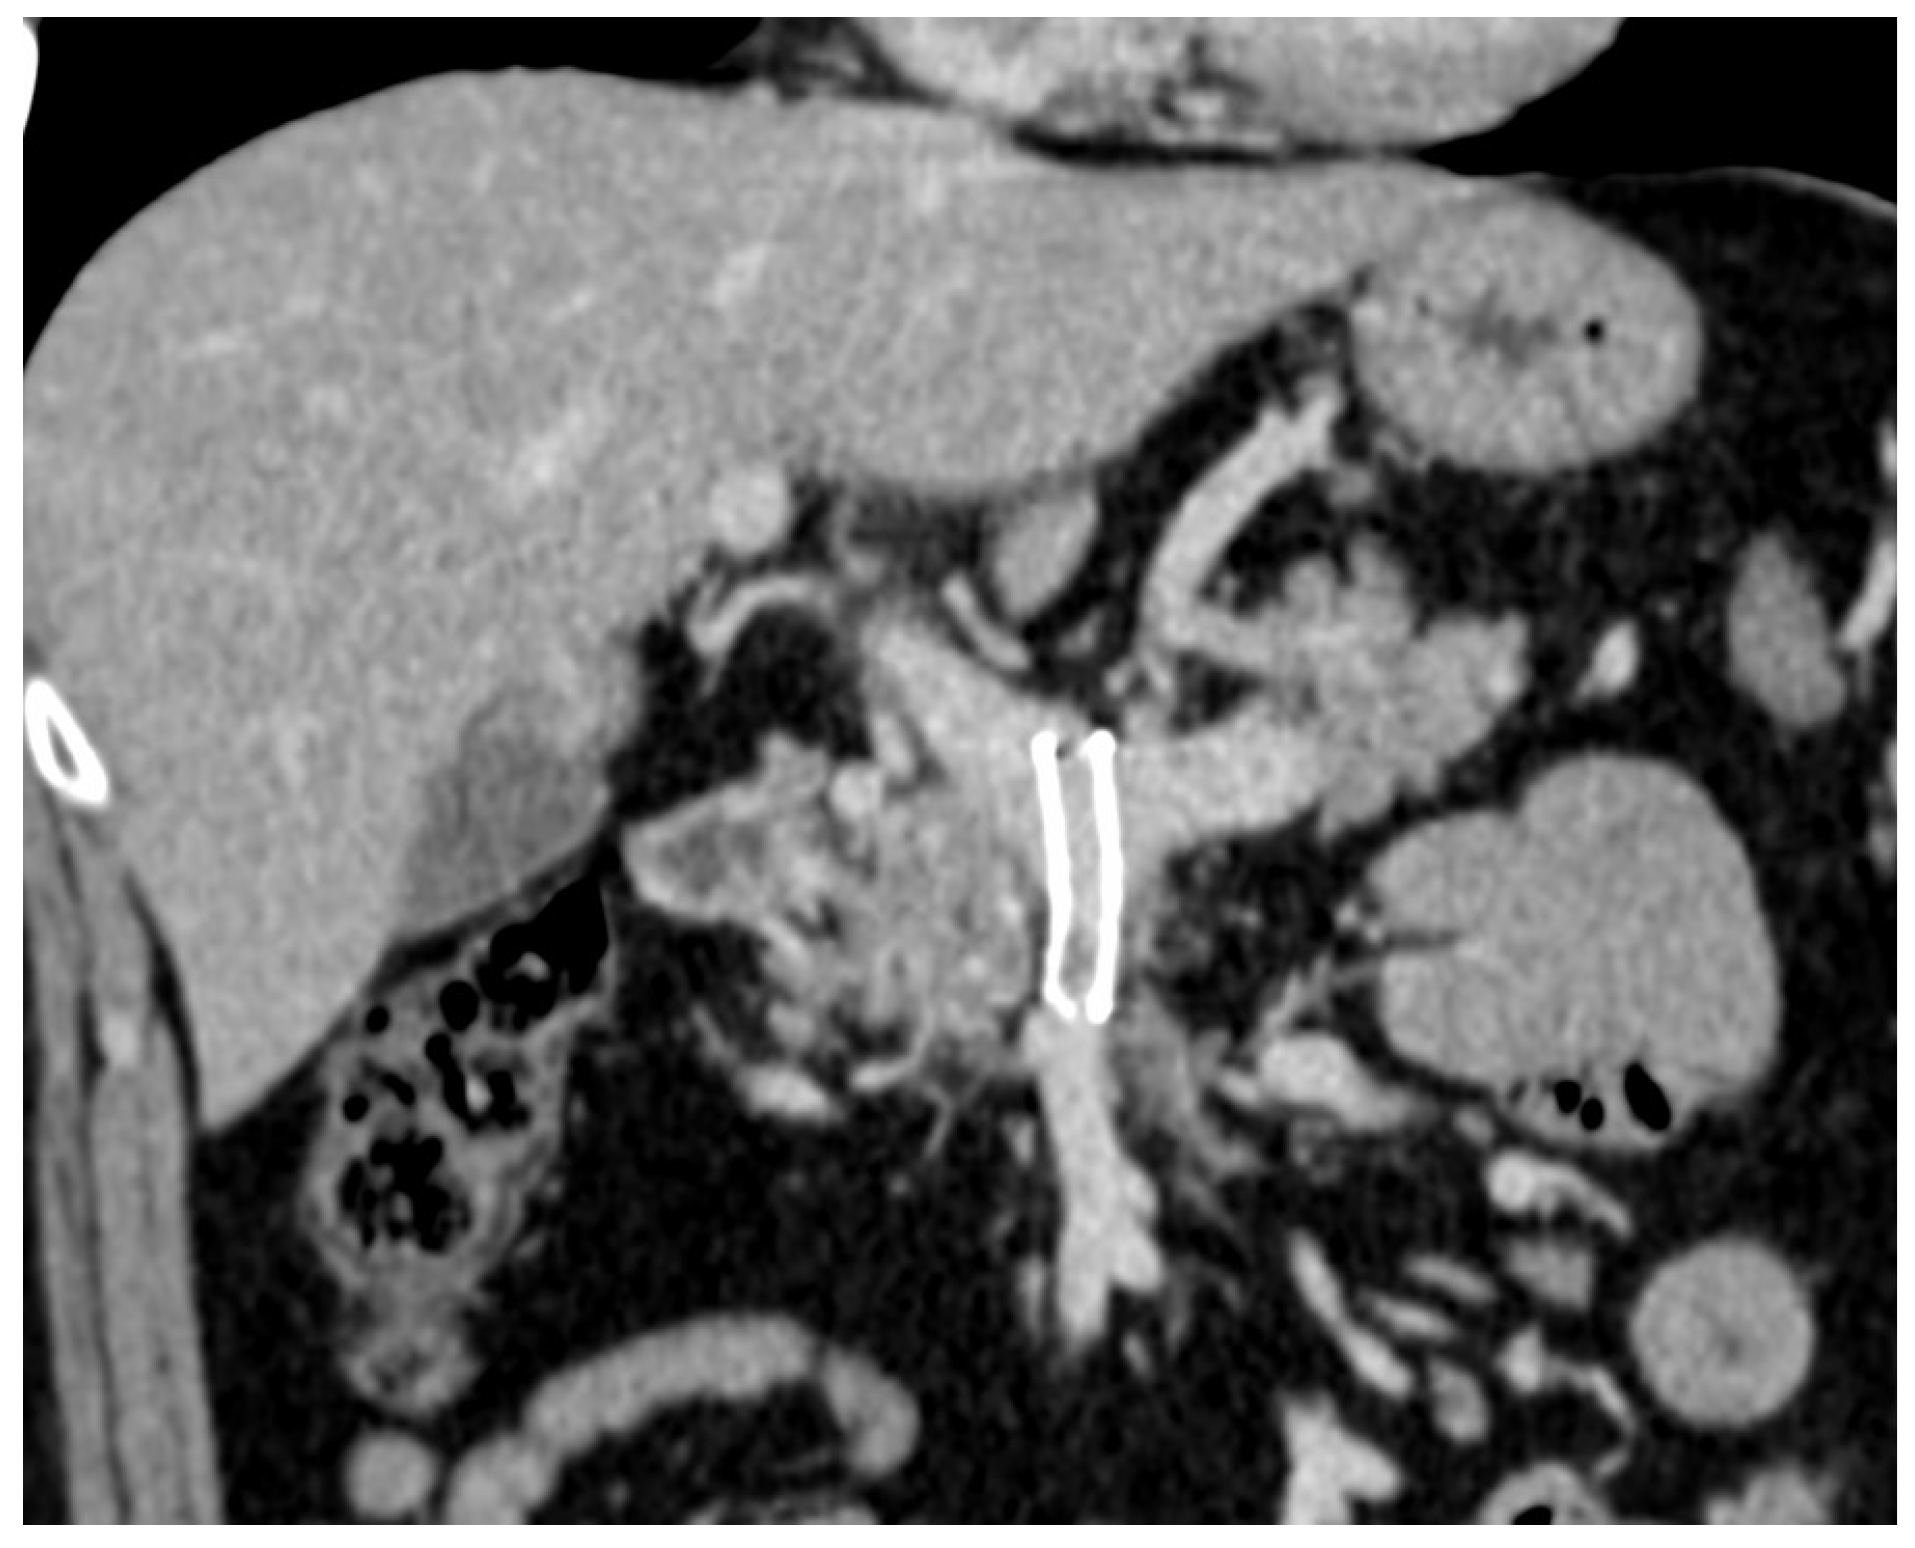

2. Case Report